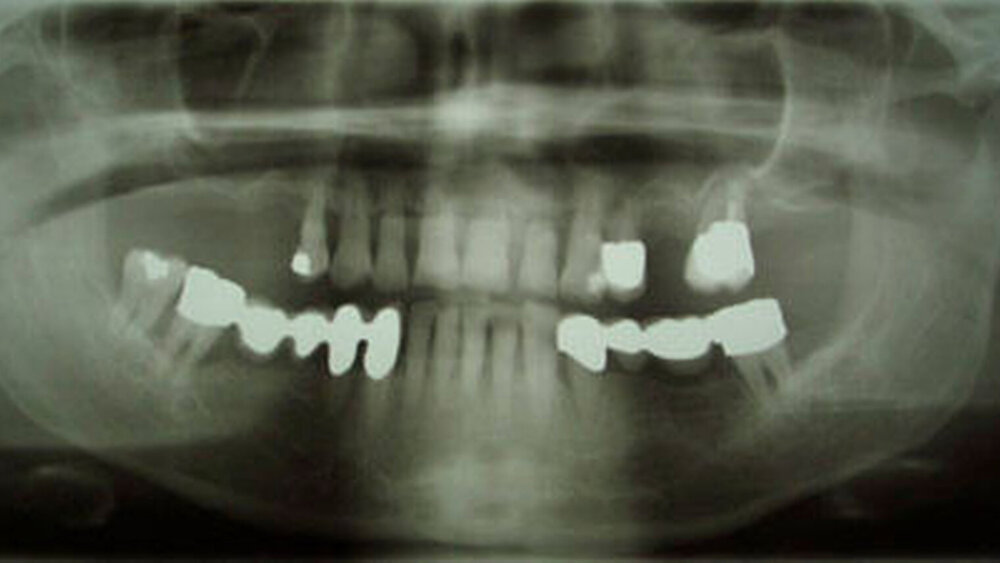

In der Querschnittsuntersuchung wurde der Zahn- und Parodontalstatus von 57 rheumatoiden Arthritispatienten und 52 gesunden Kontrollpatienten untersucht. Bei jedem Patienten wurde der Plaque- und Gingivalindex (PI, GI), Taschentiefe (TT) und klinischer Attachmentverlust (CAL) gemessen. Zusätzlich wurden potenzielle Risikofaktoren der Parodontitis, wie Rauchstatus, Bildungsgrad, Alkoholkonsum, Body Mass Index (BMI), sowie chronische Erkrankungen erfasst.

Die vorliegenden Ergebnisse zeigen, dass rheumatoide Arthritispatienten ein rund 8,05-fach erhöhtes geschätztes Risiko für Parodontitis im Vergleich zu gesunden Probanden vorweisen. Diese Daten berücksichtigen erhobene demografische sowie Lebensstilfaktoren. Anschließend wurde untersucht, in welchem Ausmaß die Mundhygiene diese Assoziation bedingt. Die Ergebnisse zeigen, dass die Mundhygiene ein wichtiger Faktor ist, jedoch nur in 13,4 Prozent die Assoziation erklären kann. Andere Parameter, wie der pro-inflammatorische Immunstatus und das signifikant häufigere Vorliegen einer sekundären Osteoporose bei Patienten mit rheumatoider Arthritis, begünstigen möglicherweise den parodontalen Attachmentverlust.